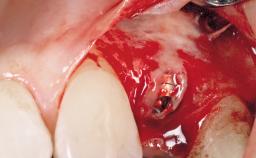

Late Placement of an Implant in a Maxillary Left Central Incisor Site

A 36-year-old female patient was referred for the replacement of the upper left central incisor (tooth 21), which had fractured. Although the tooth had been asymptomatic for many years, the crown began to loosen, at which time she presented to her dentist for an assessment. Teeth 21 and 22 had both been endodontically treated many years previously. She was a healthy individual and a non-smoker.

Bone Volume Deficient horizontally, requiring prior grafting